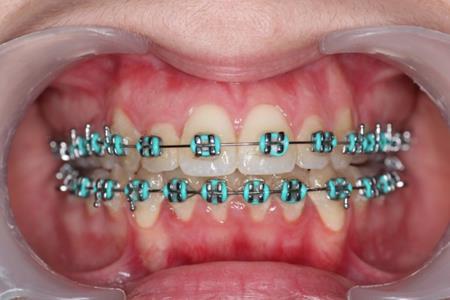

The patient, a 21-year old woman , had a convex profile , class I dental malocclusion ,anterior open bite of 4 mm . She was a mouth breather and presented tongue thrust. Her chief complain was the anterior open bite .(Figure 1)

Figure 1.Pretreatment intraoral photography

Figure 4.Intraoral photography at the start of the treatment.